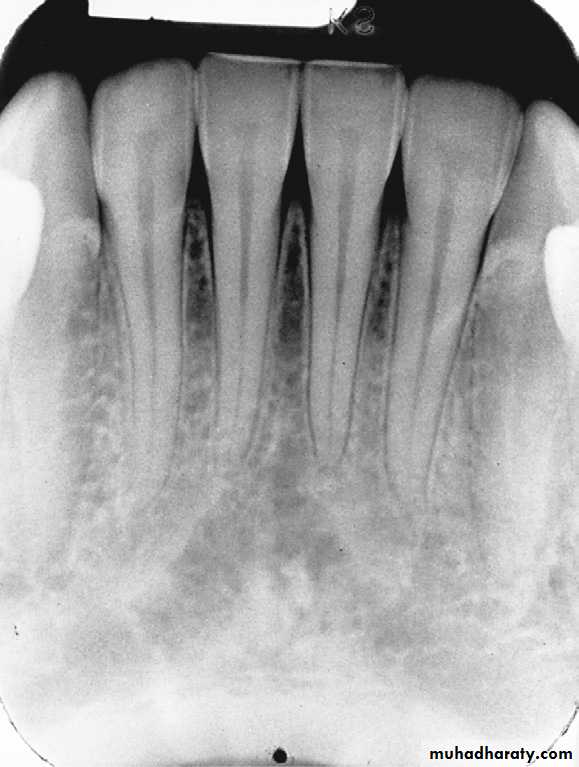

Alveolar crest: The normal healthy alveolar crest is located approximately 1.5 to 2.0 mm apical to the cementoenamel junctions (CEJs) of adjacent teeth.The shape and density of the alveolar crest vary between the anterior and posterior regions of the mouth. In the anterior regions, the alveolar crest appears pointed and sharp and is normally very radiopaque .In the posterior regions, the alveolar crest appears flat, smooth, and parallel to a line adjacent CEJs .The alveolar crest in the posterior regions appears slightly less radiopaque than that in the anterior regions

Healthy alveolar crest in the anterior region that appears pointed and highly radiopaque